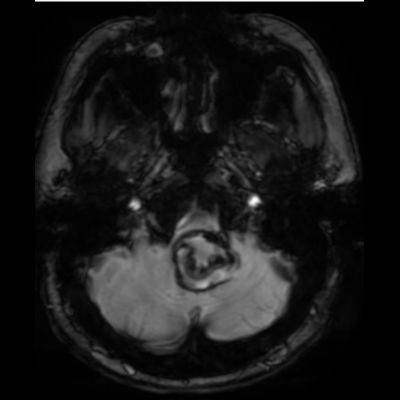

- A. Posterior fossada, T2A, T1A görüntü ve SWAN sekanslarda, 3.5 cm boyutta, düzgün sınırlı, T1A hiperintens, T2A hipointens heterojen iç yapıda kitlesel lezyon izleniyor (çember). Lezyonun serebellum ve kraniyoservikal bileşkeye bası etkisi mevcuttur (ok). Lezyon periferinde T1A, T2A ve SWAN görüntülerde hiperintens tubuler yapı bulunmaktadır (ok). Bu yapı intralezyonel “yılanvari eksantrik vasküler’’ yapıdır.

- T2 kısmen tromboze anevrizmada genellikle hipointens odaklarla heterojen, serpantin anevrizma içi damar kanalında akım boşlukları, bitişik parankimde vazojenik ödem görülebilir.

- T2 ve SWAN genellikle santral-çevresel duyarlılık artefaktları görülür.